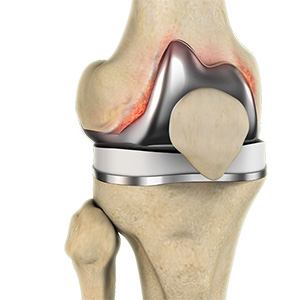

Periprosthetic Knee Infection

A very small percentage of patients (less than 1%) who undergo knee replacement may develop an infection around the knee joint. This infection is called a periprosthetic knee infection.